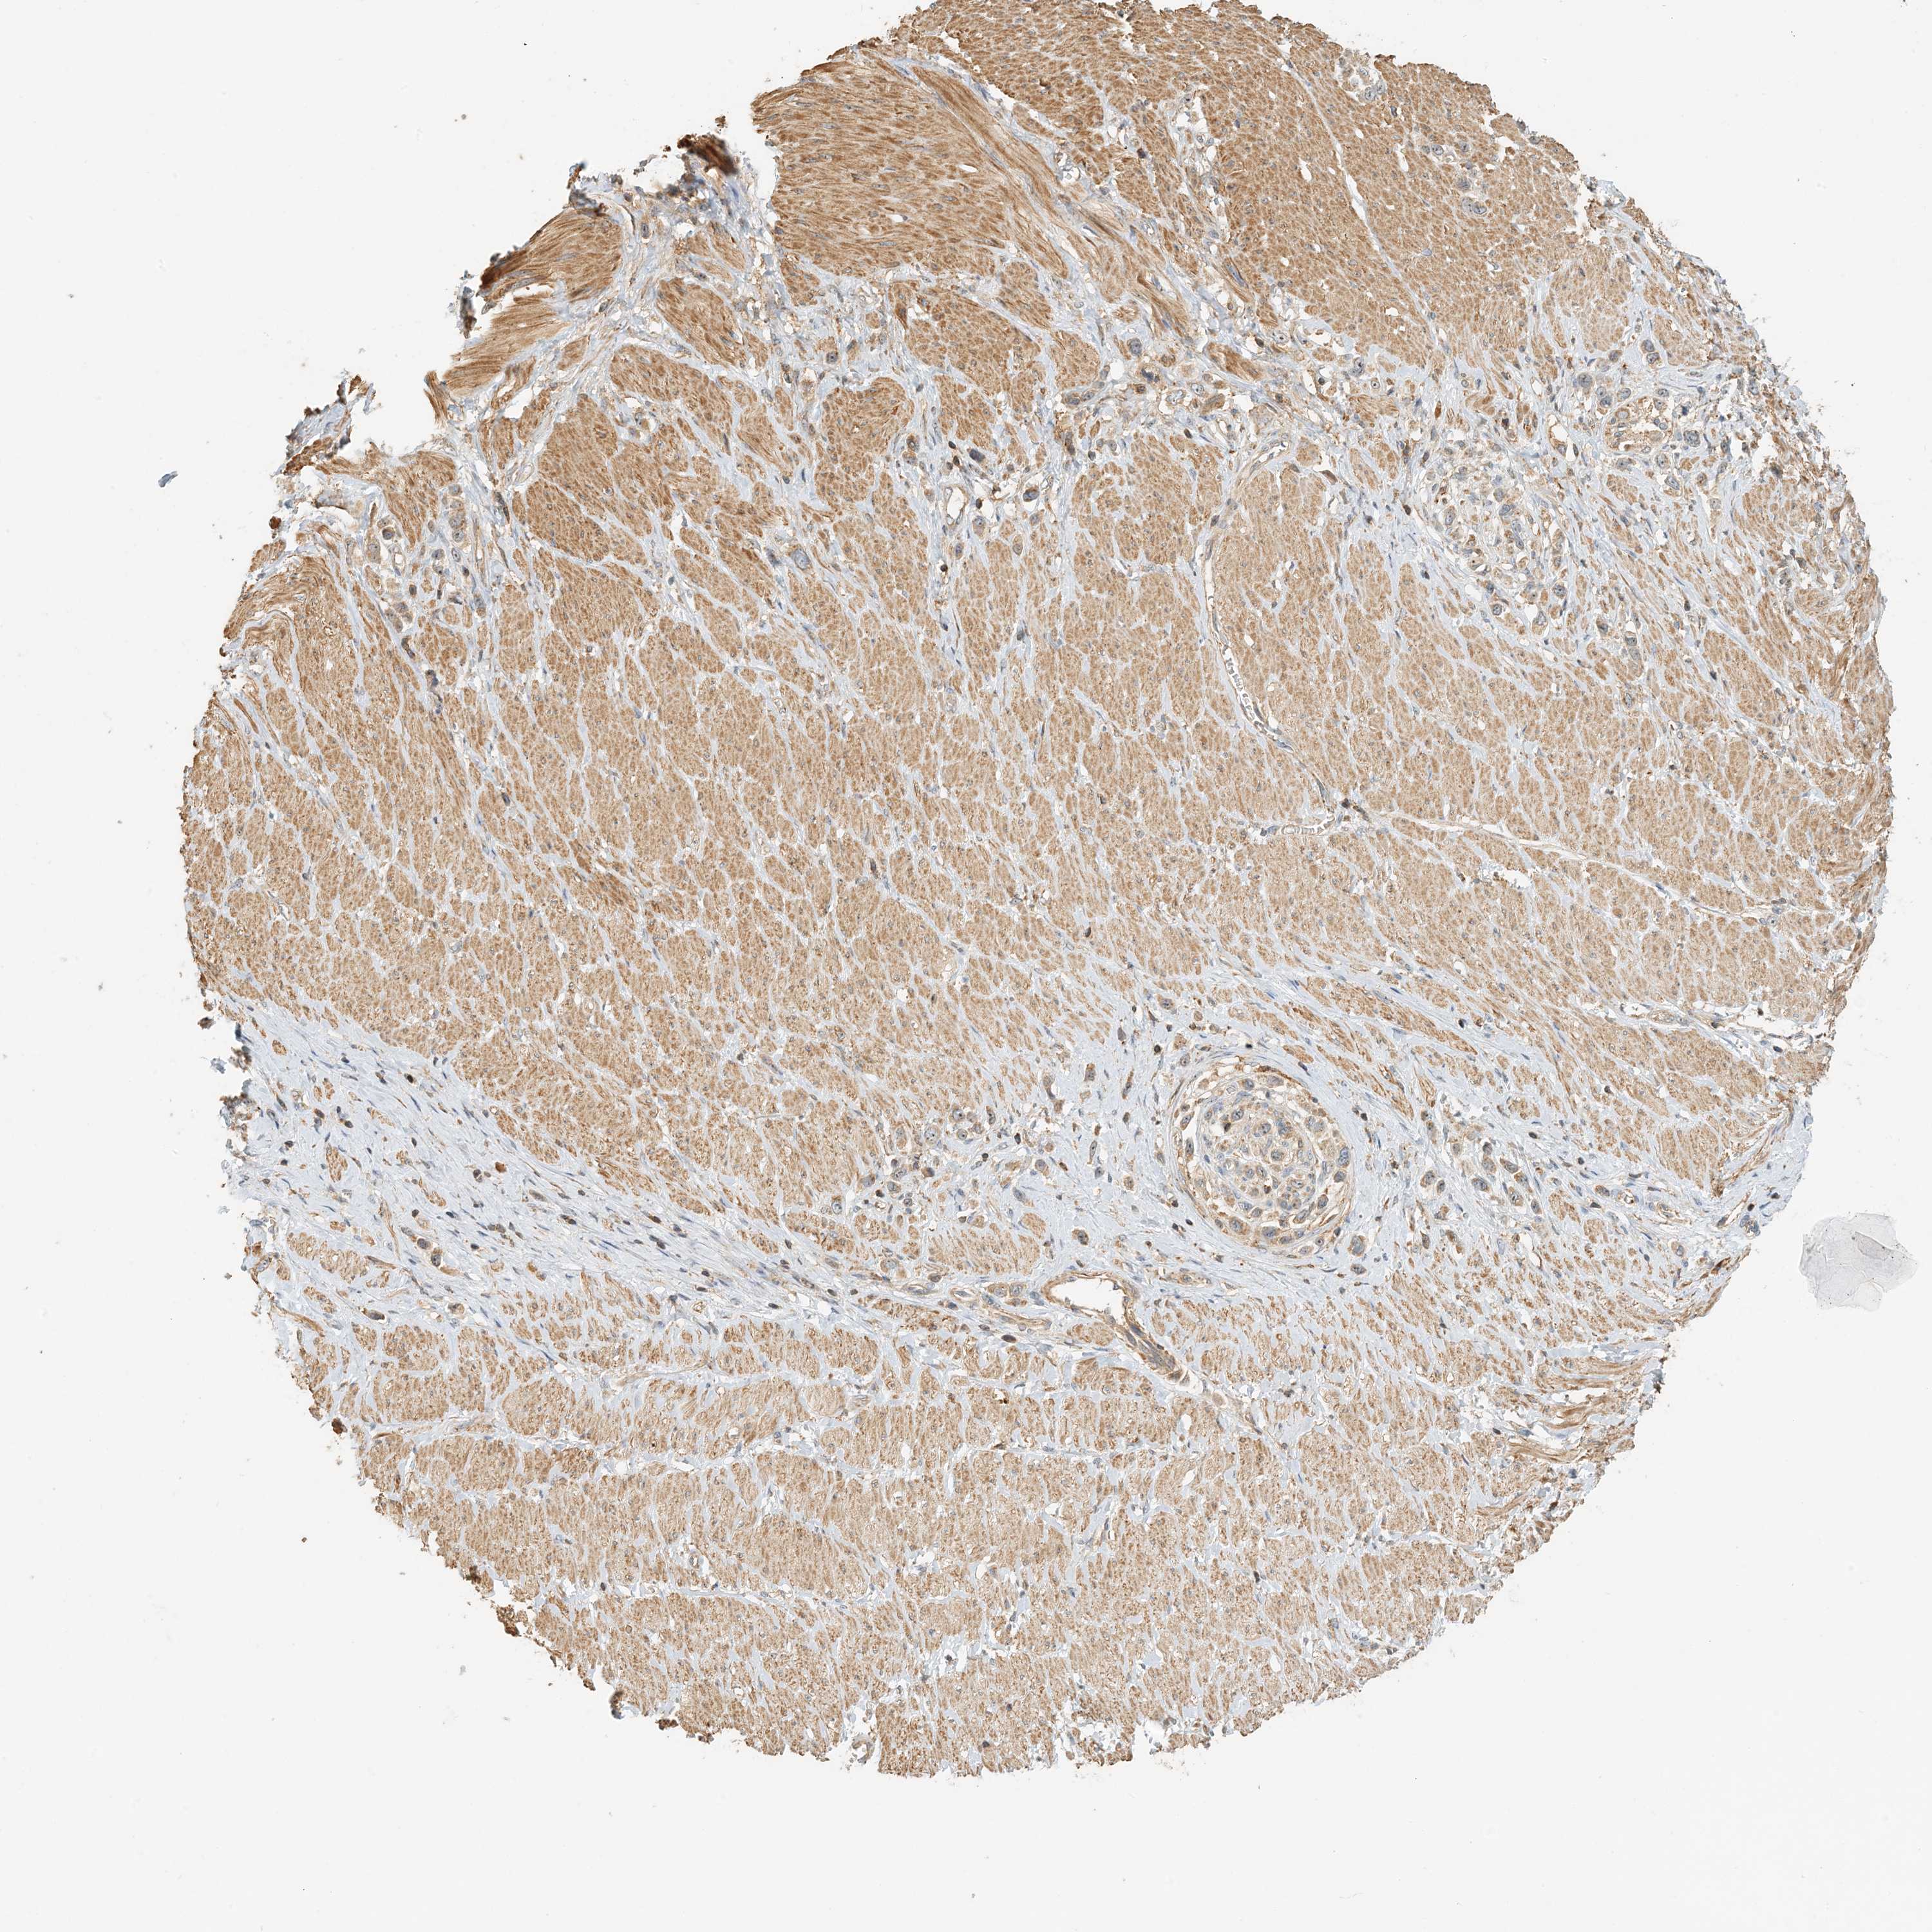

STOMACH CANCER - Protein expressioni

A mouse-over function shows sample information and annotation data. Click on an image to view it in a full screen mode. Samples can be filtered based on level of antibody staining by selecting one or several of the following categories: high, medium, low and not detected. The assay and annotation is described here.

Antibody stainingi

Antibody staining in the annotated cell types in the current human tissue is reported as not detected, low, medium, or high, based on conventional immunohistochemistry profiling in selected tissues. This score is based on the combination of the staining intensity and fraction of stained cells.

Each image is clickable and will lead to virtual microscopy that enables deeper exploration of all samples and also displays staining intensity scores, fraction scores and subcellular localization as well as patient and tissue information for each sample.

Antibody HPA035241

Staining

High

Medium

Low

Not detected

Intensity

Strong

Moderate

Weak

Negative

Quantity

>75%

75%-25%

<25%

None

Location

Nuclear

Cytoplasmic/membranous

Cytoplasmic/membranous,nuclear

Adenocarcinoma, NOS